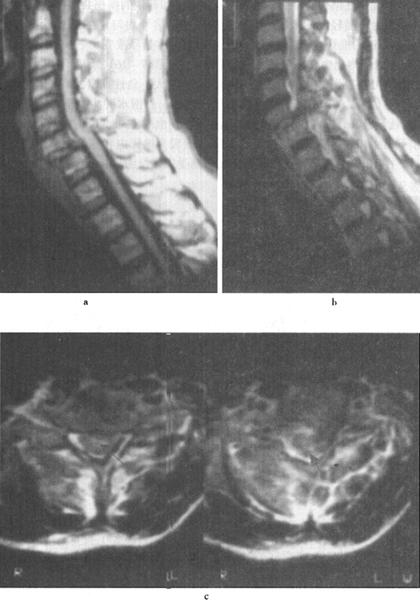

图7-15 颈髓挫裂伤:T1W(a)T2W(b)矢状面,脊髓增粒为髓水肿所致,T1W和T2W信号增高。横断面(c)脊髓内可见斑片状出血灶,硬膜外血肿T2W亦呈高信号,脊髓压迫向右后移位。颈后方软组织出血水肿,在T2W亦为高信号

(2)出血:包括脊髓内出血和硬膜外血肿(图7-14至图7-16)、硬膜下出血和蛛网膜下腔出血等。脊髓内出血是不可逆损伤,其信号改变随时间变化较大。急性期(24h内)髓内出血灶在T1WI呈中等信号或不均匀信号,在T2WI呈中央低信号出血灶,外围水肿为高信号。亚急性期(3~5d)血肿在T1WI信号逐渐升高,在T2WI信号仍较低,慢性期血肿在T1WI和T2WI均为高信号。脊髓硬膜外血肿、硬膜下出血和蛛网膜下腔出血,在MRI上表现为椎管内脊髓外的软组织增厚影,在T1WI呈不均匀低信号,在T2WI为高信号。硬膜外出血脊髓受压移位明显。